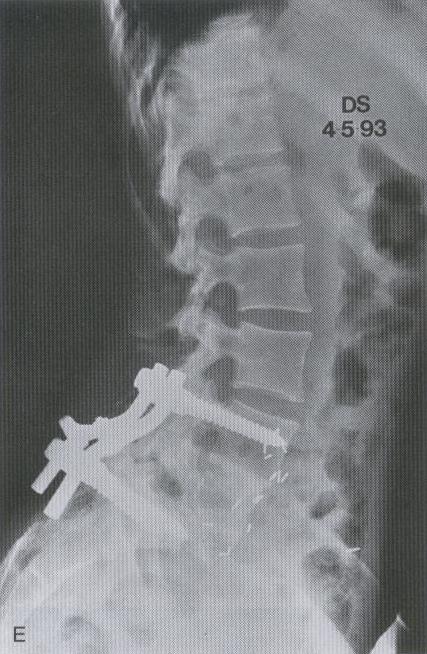

FIJACION CON IMPLANTE DE LA COLUMNA LUMBAR POR DESLIZAMIENTO VERTEBRAL